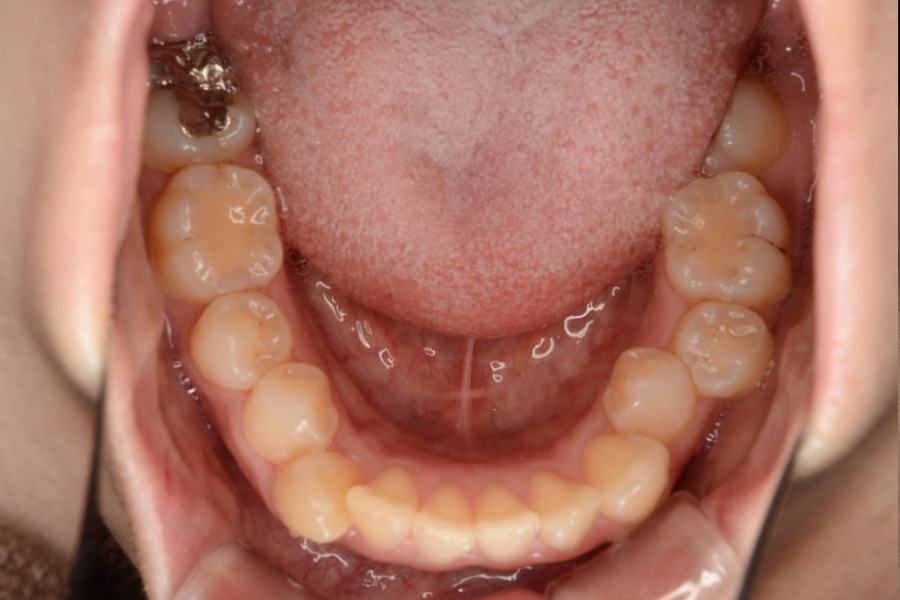

治療前

主訴 歯のガタつき

治療内容 インビザライン矯正

非抜歯